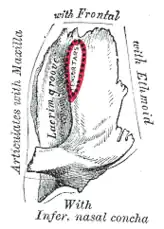

Anatomie lidské slzní kosti

U člověka je slzní kost velmi drobný plochý útvar přibližně čtverhranného tvaru. Kraniálně se dotýká čelní kosti, ventrálně a kaudálně s horní čelistí a dorzálně s lamina orbitalis čichové kosti. Částí svého povrchu směřuje do dutiny nosní, druhou plochou se otevírá do dutiny očnice. Tam se nachází oblá vertikální brázda, která se ve své spodní části rozšiřuje v jámu pro slzní vak. Z tohoto váčku vychází skrz kost slzní kanálek až do dutiny nosní. Tímto kanálkem vede slzovod, jenž odvádí slzy do nosní dutiny.[2]

Slzní kost

Slzní kost -